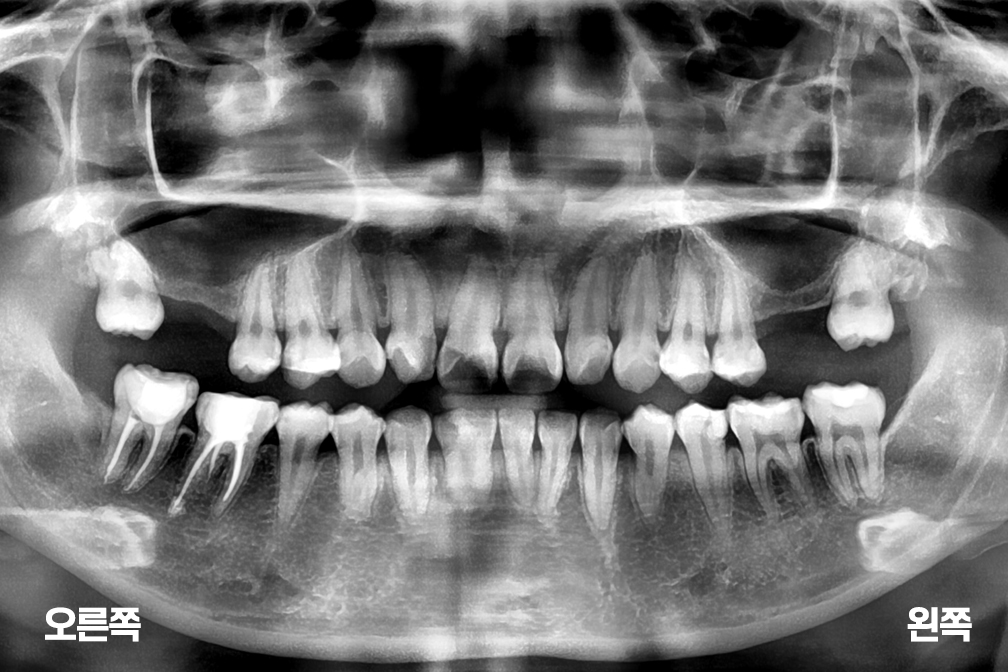

상악동거상술

위 전후사진은 이미지사진으로 실제 눈으로 보는 것과는 다를 수 있으며, 환자의 치아상태과 방법에 따라 치료결과가 다를수 있습니다.

사진의 날짜는 촬영날짜이며 치료의 기간이 아님을 알려드립니다.

치료 후 치아표면의 탈회 , 충치, 치근흡수 등의 부작용이 있을 수 있습니다.